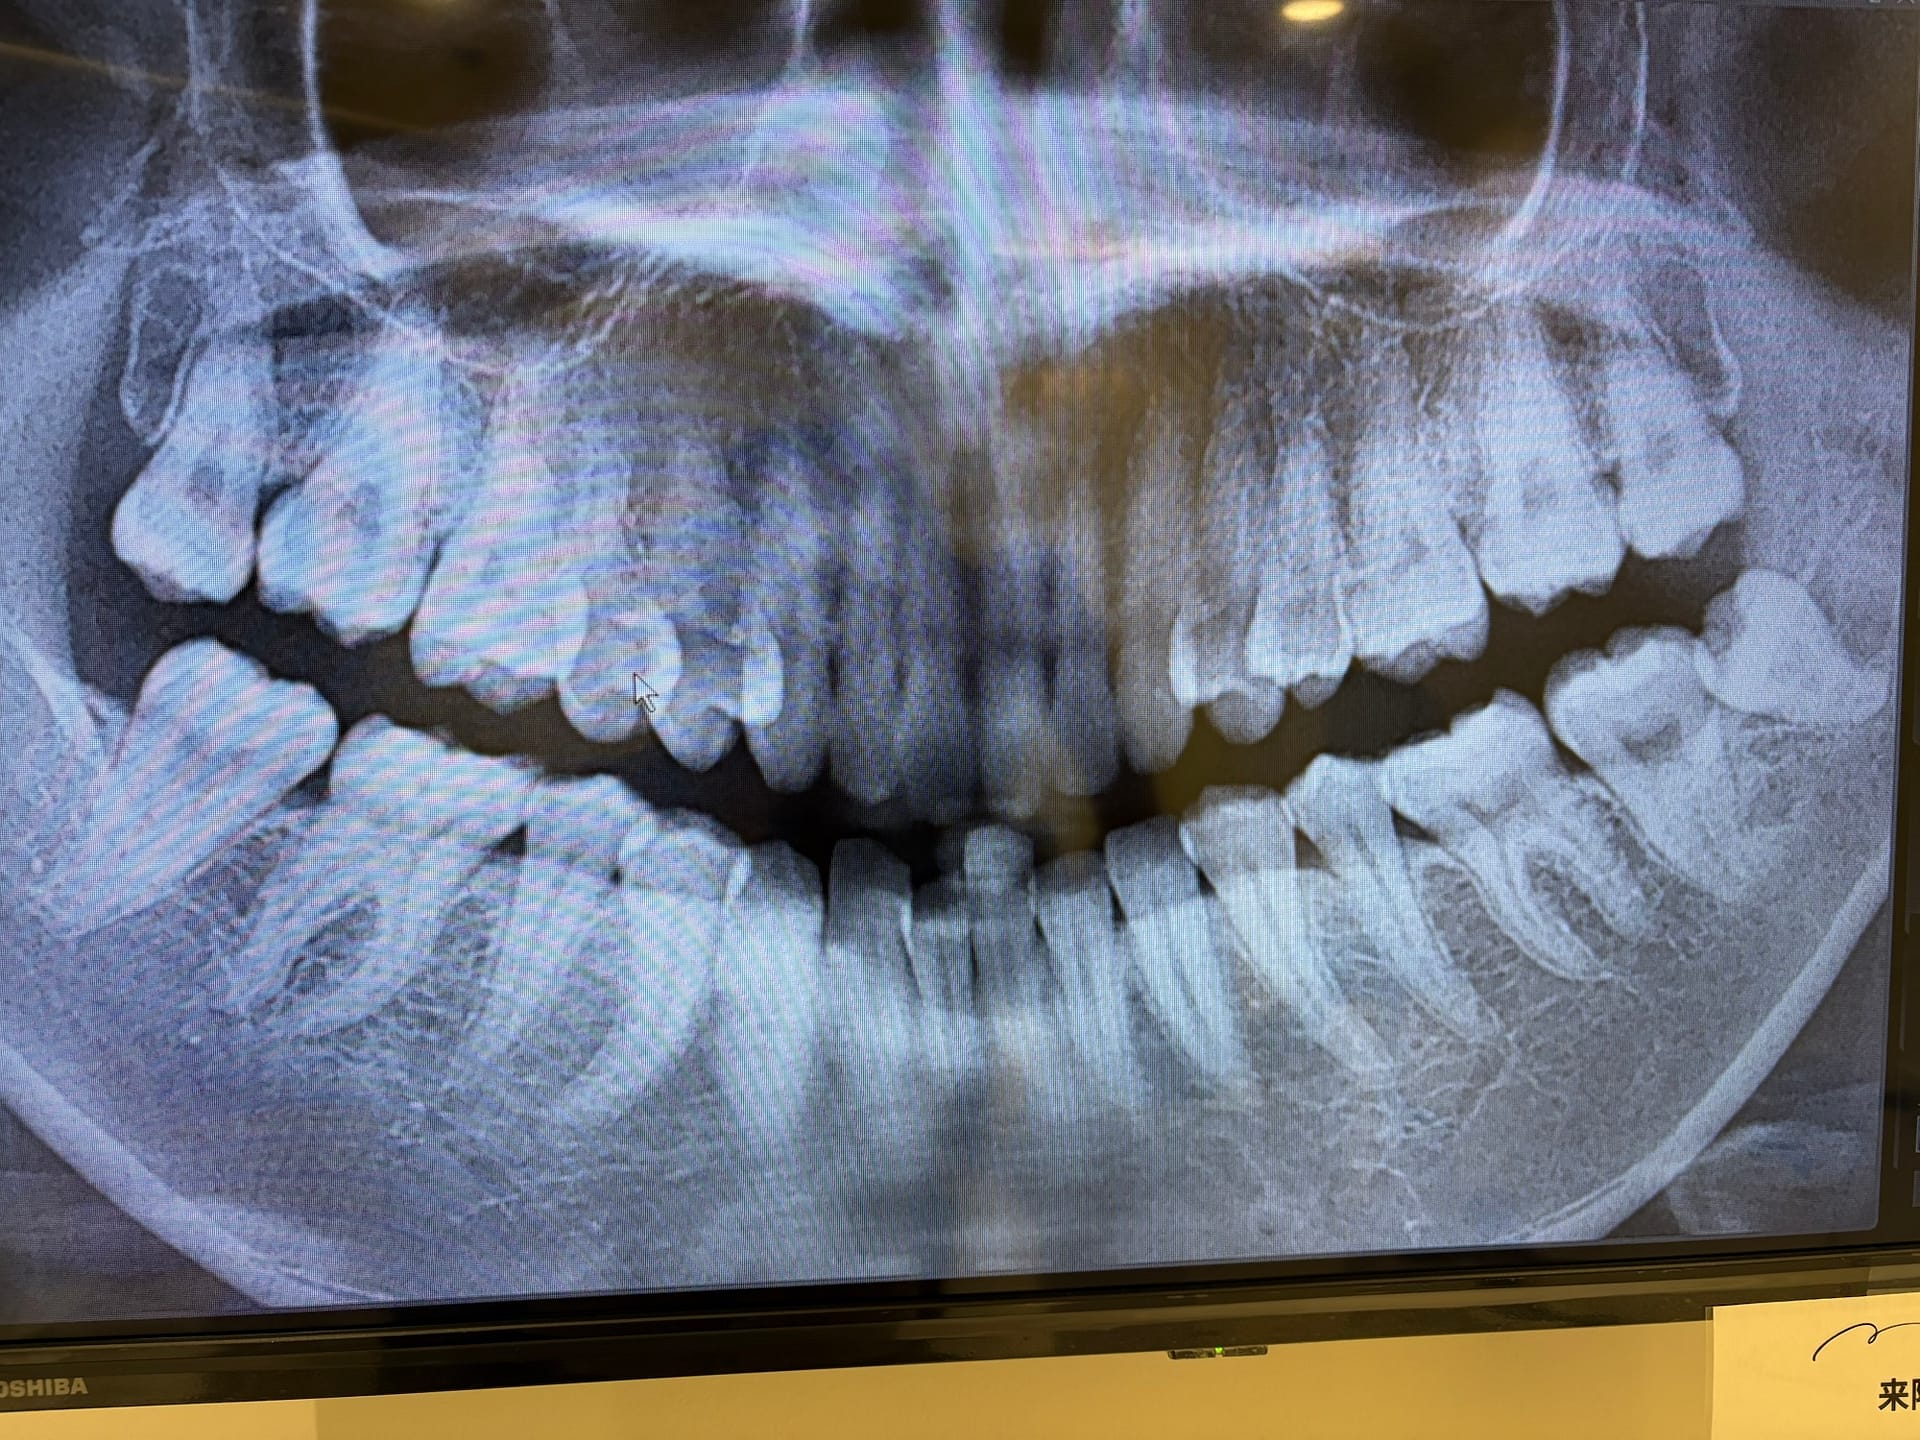

半埋伏とは、歯ぐきに一部埋まっている状態の親知らずです。

私の場合は「斜めに生えている半埋伏」だったため、

特に下の半埋伏の親知らずは、私の場合0.5cm切開してからの、斜めに分割して抜歯しました!